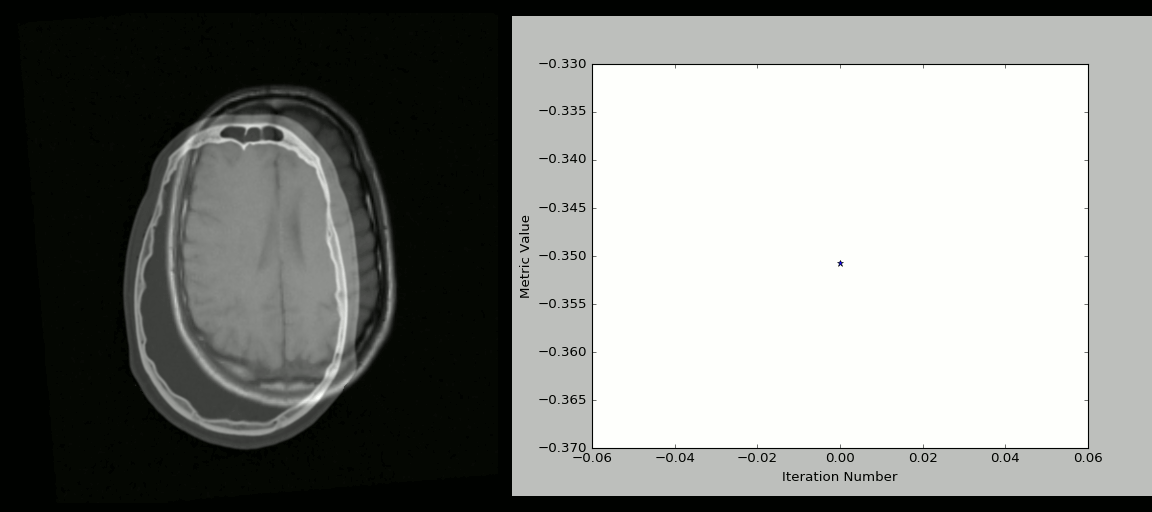

8、SimpleITK

ITK(Insight Segmentation and Registration Toolkit)是一个为开发者提供普适性图像分析功能的开源、跨平台工具套件,SimpleITK 则是基于 ITK 构建出来的一个简化层,旨在促进 ITK 在快速原型设计、教育、解释语言中的应用。SimpleITK 作为一个图像分析工具包,它也带有大量的组件,可以支持常规的滤波、图像分割、 图像配准 registration 功能。尽管 SimpleITK 使用 C++ 编写,但它也支持包括 Python 在内的大部分编程语言。

资源

有很多 Jupyter Notebooks 用例可以展示 SimpleITK 在教育和科研领域中的应用,通过这些用例可以看到如何使用 Python 和 R 利用 SimpleITK 来实现交互式图像分析。

示例

使用 Python + SimpleITK 实现的 CT/MR 图像配准过程: